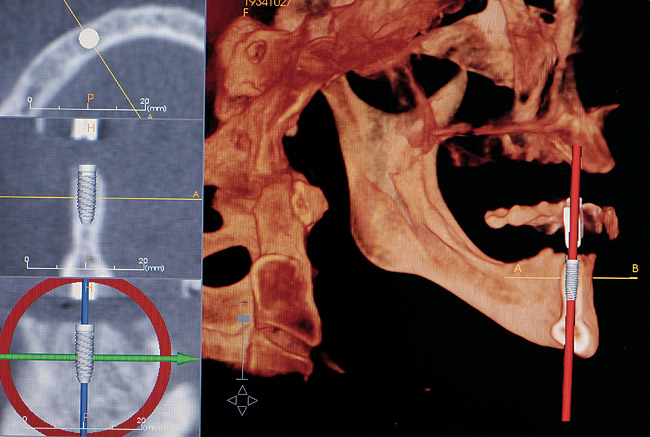

Another concern for loading of dental implants is implant alignment. When placing implants for the edentulous patient and an overlay or hybrid restoration is planned, the implants should then be placed as parallel as possible and slightly lingual to the actual tooth position. This allows establishment of normal contours of the prostheses and space for placement of the prosthetic teeth. Implants should not be placed in the central incisor region for a maxillary overlay prosthesis because this will compromise palatal contours, thereby affecting speech and tongue function. If, however, implants are planned for the partially edentulous patient and the replacement is for a natural tooth or teeth, then implants should be placed more in line with the long axis of the natural root. Teeth are designed to better handle the multitude of directional loads encountered during mastication when properly aligned on their bony base. Implants placed more in line with natural tooth roots that are properly positioned on their bony base may allow implants to better endure the various functional loads while promoting the continual physiologic bone remodeling necessary for long-term implant survival (Figure 6 and Figure 7 ). Depending on the type of anticipated function and the presence or signs of parafunctional habits, use of a maxillary biteplane/nightguard may be indicated (Figure 8). This can reduce the possibility of lateral loads, which have a detrimental effect on the dental implant(s). The biteplane is adjusted in centric relation with simultaneous occlusal contacts and shallow anterior guidance.

Figure 7  Implants placed more in alignment with natural tooth roots.

Figure 7

Figure 9: A computed tomography scan can provide additional information to aid the implant team for proper placement of the implant(s).

Figure 9